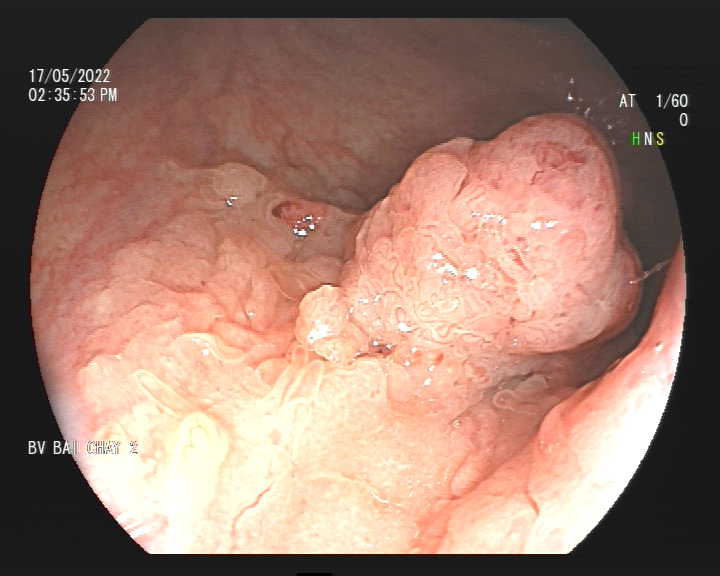

Bà được chỉ nội soi đại tràng, phát hiện polyp lan tỏa (LST) ở trực tràng - ống hậu môn, kích thước 4cm, bác sĩ nội soi đã sinh thiết làm giải phẫu bệnh có kết quả u tuyến ống nhú loạn sản độ cao. Sau khi hội chẩn, các bác sĩ quyết định điều trị cho người bệnh bằng phương pháp cắt tách dưới niêm mạc qua nội soi thay vì phải thực hiện một cuộc đại phẫu thuật. Ưu điểm của phương pháp này, chỉ cắt tách lấy khối niêm mạc bị tổn thương, để lại lớp cơ của ống tiêu hóa mà không cần phải cắt bỏ một đoạn ruột, tránh những biến chứng.

Hình ảnh polyp lan tỏa (LST) ở trực tràng